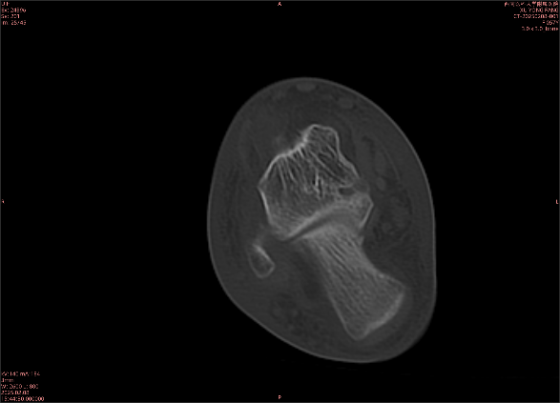

由于無骨皮質(zhì)中斷,尚不足以引起X線衰減系數(shù)的明顯改變,X線平片無異常征象;CT在顯示骨皮質(zhì)及軟組織異常方面明顯優(yōu)于傳統(tǒng)X線,特別是三維重建能夠有效的評價復(fù)雜骨折,骨外傷CT檢查應(yīng)用廣泛,但CT對隱性骨折的顯示亦極為有限。

舉例圖像

圖2

專業(yè)解釋看不懂沒關(guān)系,大家看圖1和圖2就可以了,這是同一個患者跟骨的磁共振和CT圖像,圖1的紅色箭頭指示的黑線就是磁共振圖像顯示的骨折線,一目了然。而對比圖2的CT圖像上并未顯示異常。